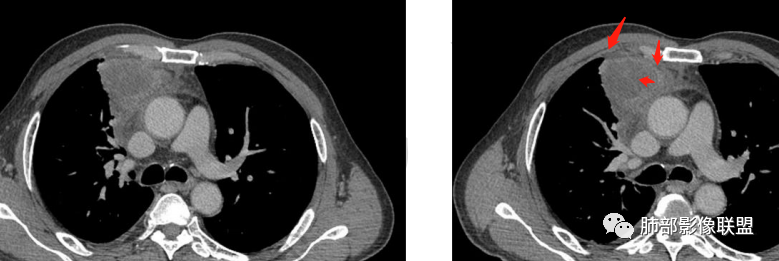

2.胸膜掀起,右侧内乳动脉略增粗,定位右前上纵隔内占位。

3.右上纵隔囊实性占位,边界清楚。中央见点状脂肪密度影,边缘见一点状钙化影,增强不均匀环形强化。

4.四天内病灶变化快,块影增大且不规则,包膜似不完整,边界不清,上份可见浸润或渗出,与周围心脏大血管及心包等间隙不清。胸水增多。

第一次的检查符合胸腺瘤影像学改变,短期内的形态学改变及突然出现的边界模糊或浸润等,符合出血或炎症。